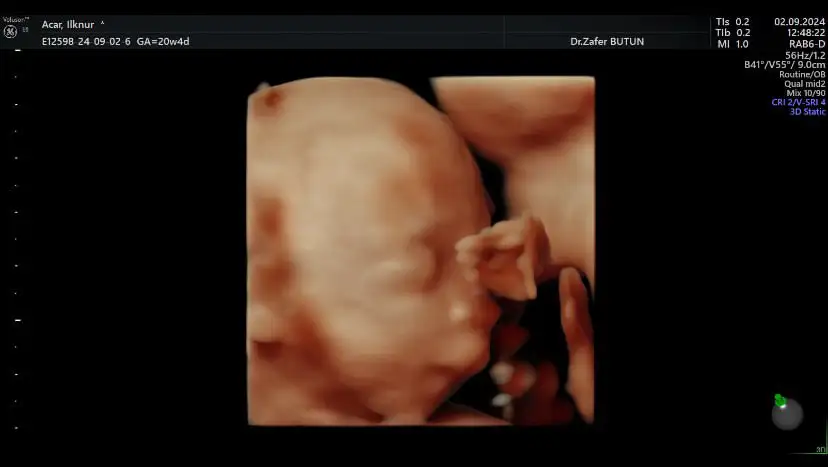

inşallah canım randevu bulamıyordum Eskişehire gelmiştik orda özelde bi doktor buldum baya uzun bakıyormuş bebiş hareket etmezse anneye hareket falan yaptırıyormuş bakalım heycanlandım bnde🥹

Biz çıktık bebiş çok hareketliydi fazla uğraştırmadı heryerine rahat rahat bakabildi doktor☺️ bi sıkıntımız yok çok şükür 🙏🏻

Ayy aman Allahım napiyorlar bunlar ya der gibi bı poz vermiş 🤣 gözün aydın cnm 🥰